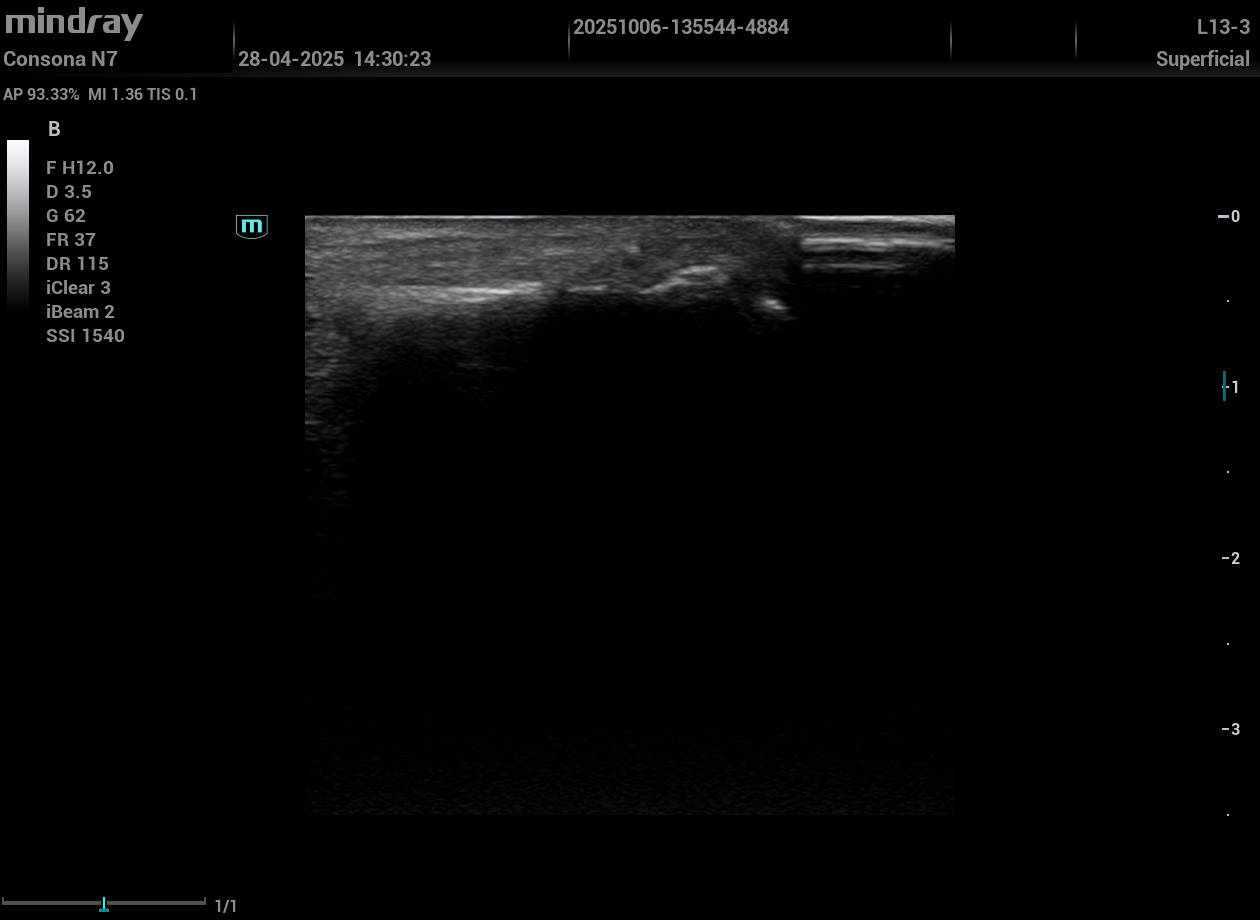

Monoartritis aguda: la ecografía articular reveló la imagen de doble contorno en maléolo interno y primera articulación metatarsofalángica, así como una imagen de acúmulo hiperecogénico compatible con tofo.